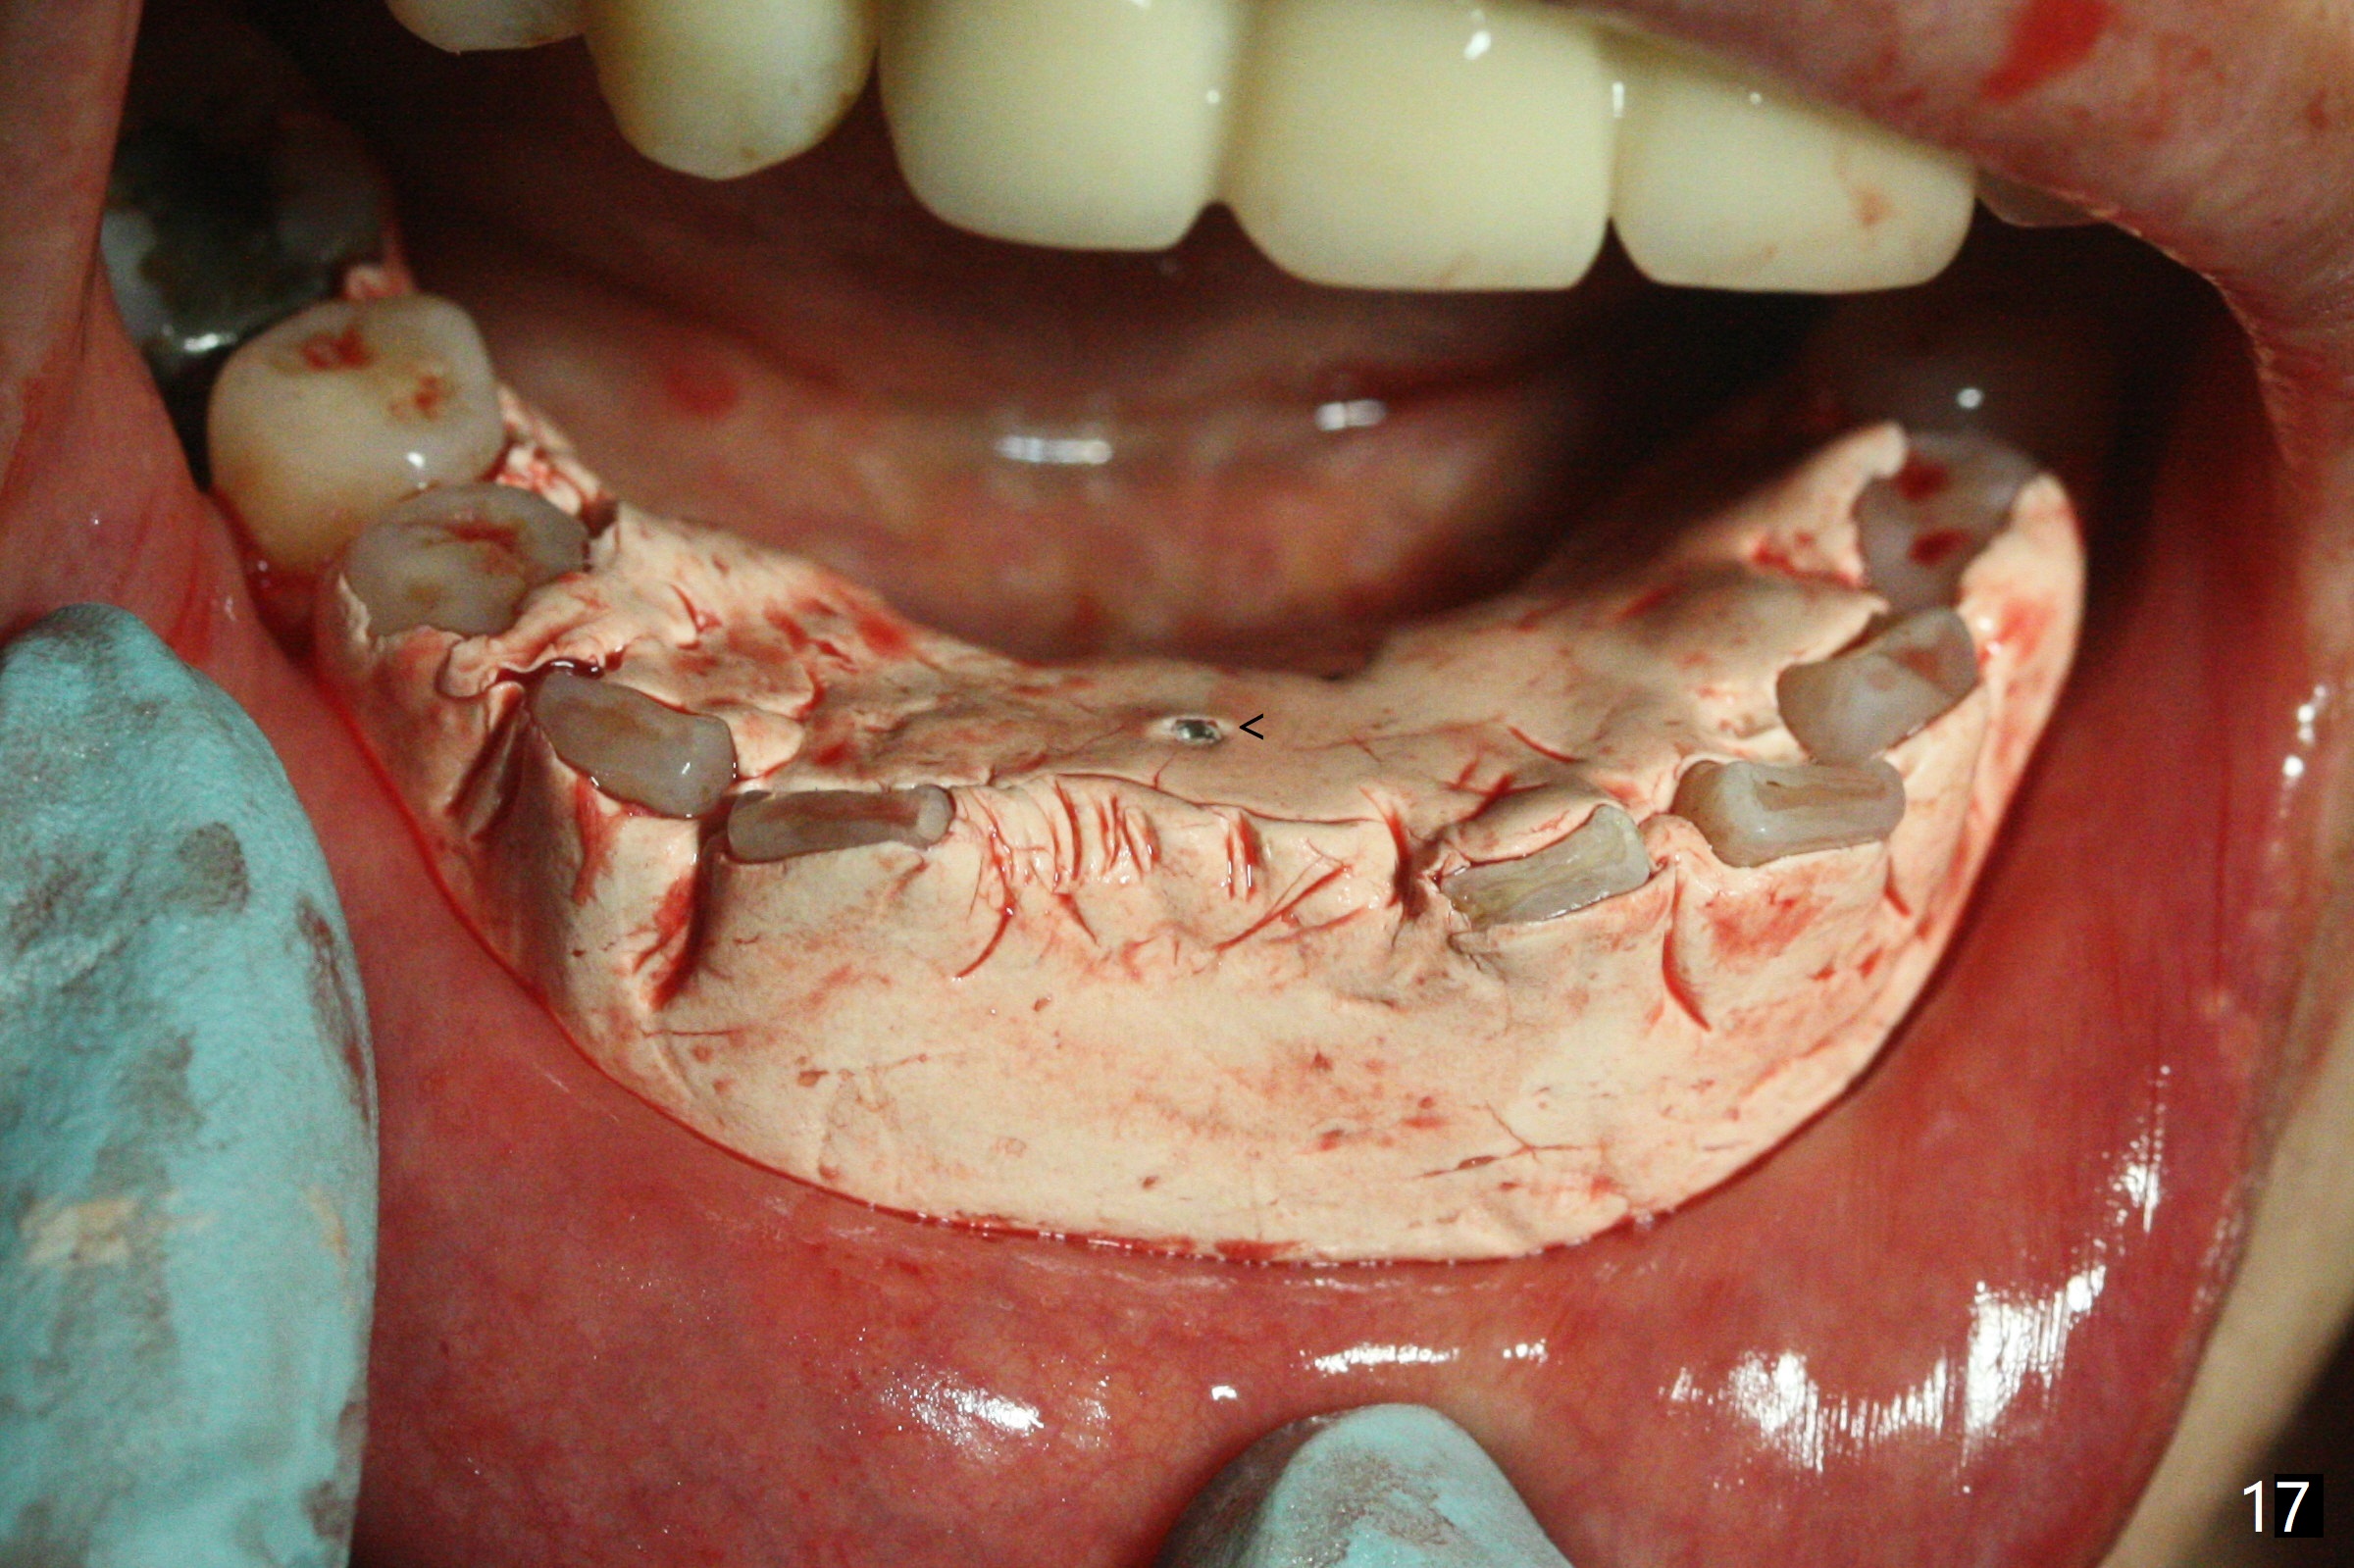

56岁女十分恐惧治疗,缺失右下1,其余切牙由于骨质吸收颊侧移位(图一:1,2),但是她不愿意拔除,同意右下1种植,牙周骨手术,植骨;植体整合后作为支抗,矫正移位下门牙。为了防止忘记舌侧瓣分离,先做舌侧切口(图二),然后颊侧瓣松弛分离(图三),包括使用前牙隧道刀(图四)切断颊侧骨膜,松弛到颊侧瓣能向舌侧牵拉3-4毫米(图五),舌侧瓣骨膜下广泛,深部分离(好像不能切断骨膜,图六),放置导板,磨平狭窄的牙槽嵴(图七:O(osteotomy)),植入2.5x12(4)毫米一段式植体(图八:故意舌侧植入,以便以后矫正),在颊侧骨板打多个出血洞(图八:箭头),然后把在平的器皿上形成的粘性骨板(sticky bone,图九),放置于植体和移位切牙周围(图十),接着使用消毒过的橡皮障punch(图十一(纸头相当于PRF膜;事先给助手示范))在三个PRF膜(图十二)打洞,套在植体和门牙上(图十三: 箭头),防止膜(图十四)和骨块(图十五,十六:*)移位,最后还必须使用最原始方法牙周敷料保护伤口(图十七)。术后9天,舌侧牙周敷料脱落,伤口稍微裂开(图十八)。术后18天撤除敷料,伤口裂开处有新鲜肉芽组织生长(图十九(*:下面是填入的骨粉,将是增宽的牙槽嵴(如果你是乐观主义者)),二十)。病人十分感激我们帮助她度过难关。她的确有sleep apnea,否定tongue thrust。术后三个月植体周围没有明显骨质吸收(图二十一至二十三),左下1,2轻度反合(图二十四),植体周围软组织健康(图二十五),5-5安置矫正器(图二十六,二十七,12 niti)。一周后下切牙向舌侧移动(图二十八),左下1,2反合纠正(图二十九)。再一周变化不大(图三十),植牙圈有些松动,两周后将重做临时牙冠,槽往舌侧移动。结果病人提前回来,植牙槽舌侧移位。一周后右下2不适(图三十一),尝试近中牵引(图三十二)。